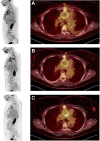

Case summary: A 39-year-old woman with hypertension and Darier disease suffered an acute type A aortic dissection, requiring emergency operation with a Dacron graft. Twenty-five days post-operatively, she developed pneumonia and staph hominis was isolated in blood cultures and Bronchoalveolar Lavage. Following completion of antibiotics, multiple relapses occurred during a 6-month period, each time treated with appropriate antibiotic therapy. An 18F-fluorodeoxyglucose positron emission tomography computerized tomography showed persistent graft uptake and re-operation was performed. At 22 months of follow-up, the patient remains asymptomatic and the 18F-FDG PET/CT shows significant reduction in FDG uptake.